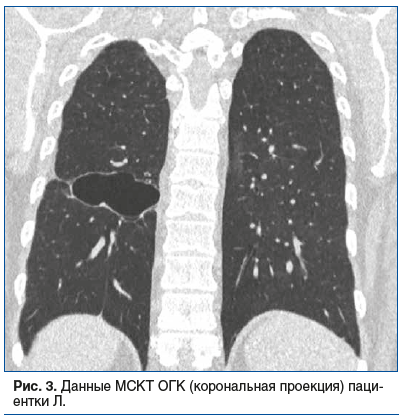

По данным МСКТ ОГК в динамике изменений нет, сохраняется полость в нижней доле правого легкого (рис. 3).

Учитывая отсутствие бактериовыделения и клинико-рентгенологической динамики на фоне лечения, диагноз туберкулеза взят под сомнение, рекомендована лечебно-диагностическая операция. В связи с сохраняющейся лейкопенией при возобновлении специфического лечения рекомендовано отменить противотуберкулезные препараты до получения результатов гистологического и микробиологического исследования операционного материала. Проведена видеоассистированная торакоскопическая нижняя лобэктомия справа. Гистологическое заключение: порок развития легкого с формированием бронхоэктазов, пневмосклероз. При микробиологическом исследовании операционного материала КУМ и ДНК МБТ не получены, туберкулезная этиология процесса не подтверждена. Диагноз туберкулеза легких снят.

Приведенное наблюдение демонстрирует гипердиагностику туберкулеза и соответственно ошибки в трактовке данных КТ. В результате только морфологическая верификация привела к установке правильного диагноза.